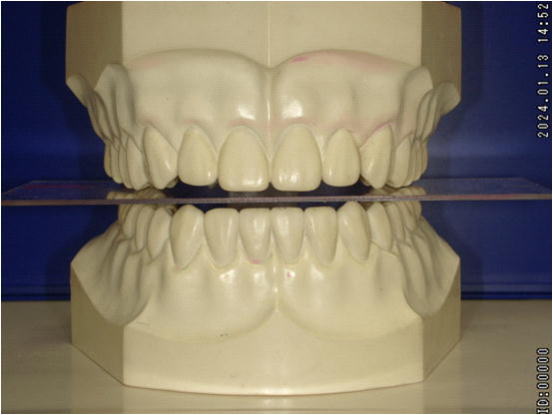

【正常な咬合関係】 |

正常な噛み合わせは、正中が合っており、左右ほぼ対称です。

前後の噛み合わせも平面的であるため、ズレることなくしっかり咬むことが出来るわけです。 |